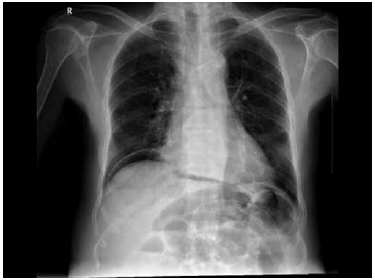

Homem de 38 anos dá entrada no pronto-socorro, referindo forte dor em todo o abdome há duas horas, de início súbito, sem fatores de melhora. Há duas semanas, está em tratamento para úlcera no duodeno. Encontra-se consciente, descorado ++/++++, eupneico. PA: 90 x 40 mmHg; P: 98 bpm. Ao exame físico do abdome: plano, com resistência voluntária à palpação, DB + difuso, com sinal de Jobert presente. RHA + normais. Após as medidas de suporte clínico e coleta de exames laboratoriais, foi realizada radiografia simples de abdome (demonstrada a seguir).

A conduta para com o paciente deverá ser